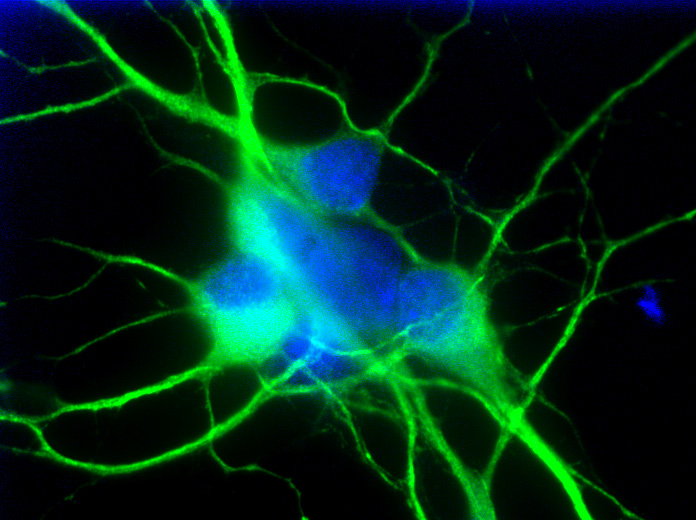

The image below shows neurons exposed to deprivation of oxygen and glucose, imitating the conditions of an ischemic stroke.